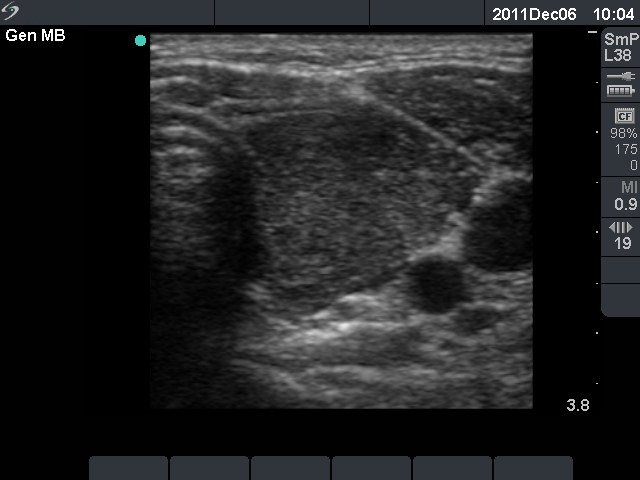

First investigation 6 months after delivery (first and second rows of images)

Clinical presentation: a 22-year-old woman was referred for an evaluation of a newly discovered hypothyroidism. She had fatigue and hair loss. She has been delivered 6 months before present investigation.

Palpation: the thyroids were enlarged and firm.

Functional state: hypothyroidism with TSH 47.7 mIU/L.

Ultrasonography: the thyroids were hypoechogenic without any nodule. The vascularization was increased.Cytology resulted in Hashimoto's thyroiditis.

Clinical diagnosis: hypothyroidism, post partum thyroiditis.